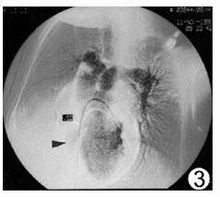

三尖瓣下移畸形三尖瓣下移畸形是一種罕見的先天性心臟畸形。1866年Ebstein首先報導一例,故亦稱為Ebstein畸形。其發病率在先天性心臟病中占0.5~1%。三尖瓣下移畸形系指三尖瓣畸形,其後瓣及隔瓣位置低於正常,不在房室環水平而下移至右心室壁近心尖處,其前瓣位置正常,致使右心房較正常大,而右心室較正常小,可有三尖瓣關閉不全。此類畸形常合併卵圓孔開放或房間隔缺損以及肺動脈狹窄。由於右心房內血量較多,壓力增高,其所含血液部分經房間隔缺損或卵圓孔流入左心房,部分仍經三尖瓣入右心室,因肺動脈狹窄,進入肺循環的血量減少,故回入左心房的動脈血量也少,此時再與自右心房分流來的靜脈血混合,經二尖瓣而入左心室及體循環

。詳細見三尖瓣下移畸形。